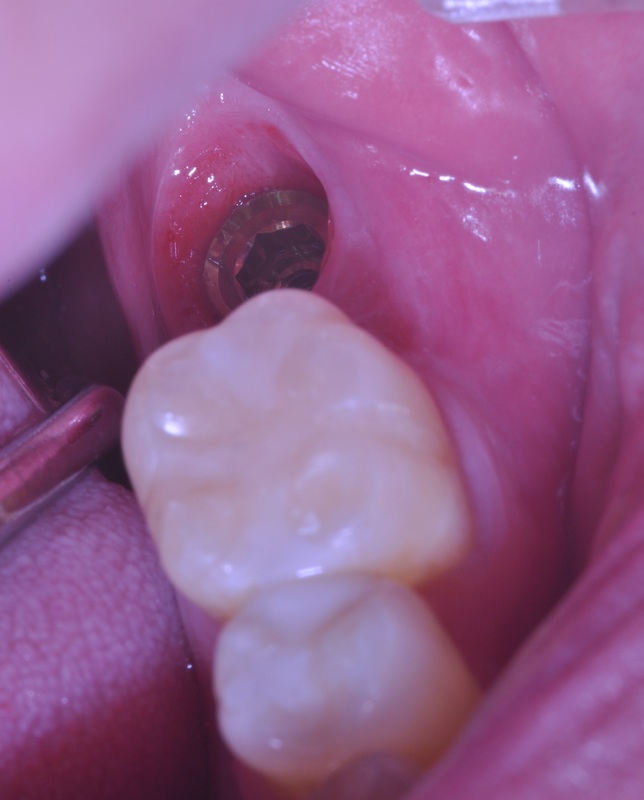

IMMEDIATE LOWER MOLAR REPLACEMENT

This type of cases Dr. Andrews encounters on a regular basis.

A 30 year old was concerned with the discomfort next to his impacted wisdom tooth and pain associated with cold and hot temperatures around the decayed back teeth.

After thorough dental examination Dr. Andrews recommended to extract the wisdom tooth (#17) and the second molar (#18) due to severe decay and poor prognosis for both teeth and to replace the second molar (#18) with a dental implant.

During only one 45-minute surgery both teeth were removed, a minor bone graft was placed and a wide-diameter (7 mm) dental implant was immediately inserted to replace the second molar. Four months later , #18 implant was restored with an all-ceramic crown.

Revolutionary digital scanning technology and CAD/CAM fabrication process had been used by Dr. Andrews to create an ideal emergence profile, ideal bite and natural anatomy for the crown.

Cavities on other teeth were treated with mercury-free, bio-mimetic white composite fillings.